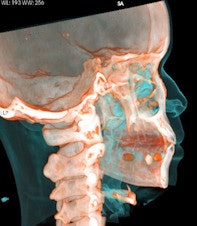

Capsules holding cocaine are of different densities. It is important to perform window-level adjustments to detect drug containers, according to the authors. It also helps for a radiologist to know what the typical size and appearance are of different cocaine containers. With this knowledge, they can be better distinguished from normal intestinal gas, calcifications, scybala, and other foreign bodies.